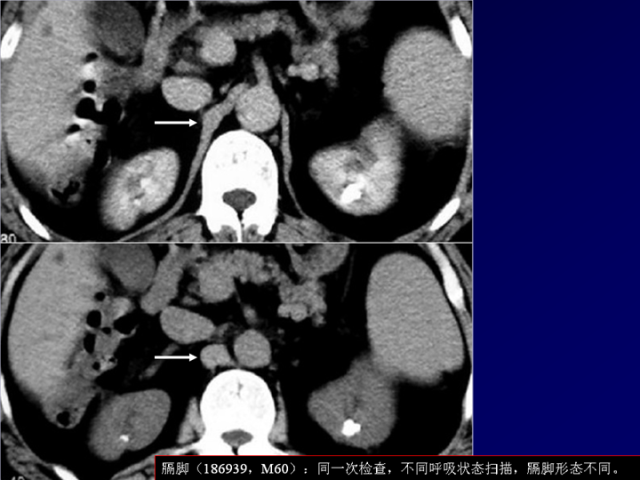

膈肌角解剖及常见变异

作者:王俭 上海长征医院